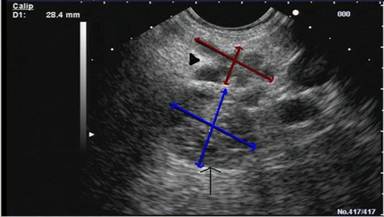

A 63-year-old white male presented with six-week history of intermittent, mild, right flank discomfort. His past medical and surgical history was unremarkable. He denied significant alcohol consumption. His physical examination apart from moderate obesity was unremarkable. A biphasic CT scan of abdomen performed for evaluation of pain revealed a 2 cm water density lesion located in the posterior pancreatic tail (Figure 1). His serum CA 19-9 and serum amylase levels were normal. He was referred to us for further evaluation of incidentally found pancreatic cystic lesion. He underwent endoscopic ultrasound (EUS) which revealed three cysts ranging in size from 4 mm to 10 mm in pancreas body (which were not identified on CT) and a multi-loculated cystic lesion measuring 2.1x1.4 cm (lesion #1)located in the pancreas tail (corroborating the CT findings). The main pancreatic duct caliber was normal. The sonographic features were suggestive of multi-side branch-IPMN (Figure 2, arrowhead). Immediately inferior to the largest multi-side branch-IPMN lesion and adjacent to the left kidney, a well-circumscribed, more solid-appearing lesion with anechoic (microcysts) intervening spaces was seen (lesion #2) (Figure 2, arrow). This lesion was not identified on his CT scan.

Lesion #2 measured 22 mm in the greatest diameter. Based on sonographic features of lesion #2; a differential diagnosis of likely serous cystadenoma versus other cystic solid lesions (neuroendocrine tumor) was rendered. An EUS guided fine needle aspiration (EUS-FNA) using a 22 G needle of lesion #1 yielded 3 mL of clear viscous fluid with an elevated CEA (203.7 ng/mL) and amylase (17,514 U/L) levels. EUS-FNA cytology was consistent with IPMN. The immediately inferior to the multi-side branch-IPMN location of the lesion #2 precluded safe and uncontaminated advancement of the FNA needle. A subsequent distal pancreatectomy and splenectomy confirmed synchronous microcystic serous cystadenoma and multi-side branch-IPMN (Figure 3). Patient remains asymptomatic at 18-month follow-up.

Figure 2. Endosonographic image displaying coexistent IPMN (arrow-head) and microcystic serous cystadenoma (arrow). |